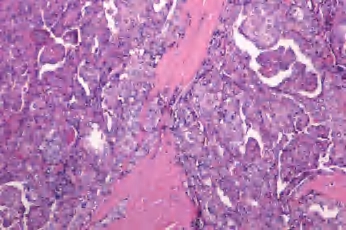

(2)大滤泡亚型:罕见,主要或全部由大滤泡构成,常与增生性结节或大滤泡腺瘤混淆;但滤泡细胞含有大而亮的核和核沟、核内假包涵体。此亚型很少见到淋巴结转移(图3-46、图3-47)。

图3-46 甲状腺乳头状癌,大滤泡亚型

图3-47 甲状腺乳头状癌,大滤泡亚型